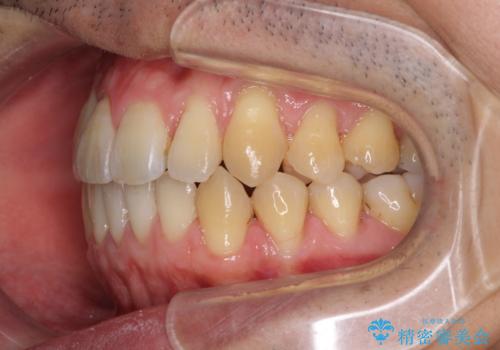

- 上下の前歯の反対咬合を気にして来院された患者様です。

インビザラインを用い、下顎はIPR(歯と歯の間を削る)と歯列全体を後方に移動させ、上顎は前歯を持ち上げることで、反対咬合を改善していくこととしました。

八重歯の歯根が見えている点も気になっているので、矯正歯科治療後に歯肉移植による根面被覆を行うこととしました。

インビザラインによる反対咬合の改善は、上の歯が下の歯を乗り越えていく期間に咬み合わせが非常に不安定となり、治療が長期化することがあります。

また、ワイヤー矯正と異なり歯軸改善の強い力を前歯にかけるため、反対咬合で裏側にある歯の歯肉が退縮しやすくなります。

矯正治療により元々気になっていた八重歯と、反対咬合が改善された歯の2本に対して根面被覆を行い、審美面の改善も達成しました。